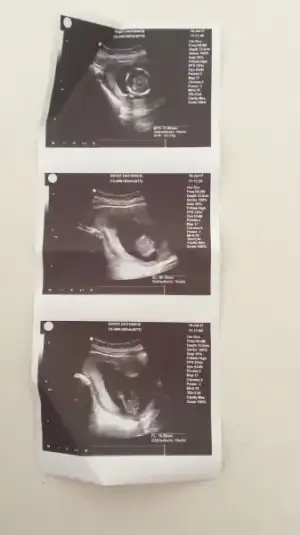

Varmı bugun benim gbı kontrole gtcek olanlarrrrrr